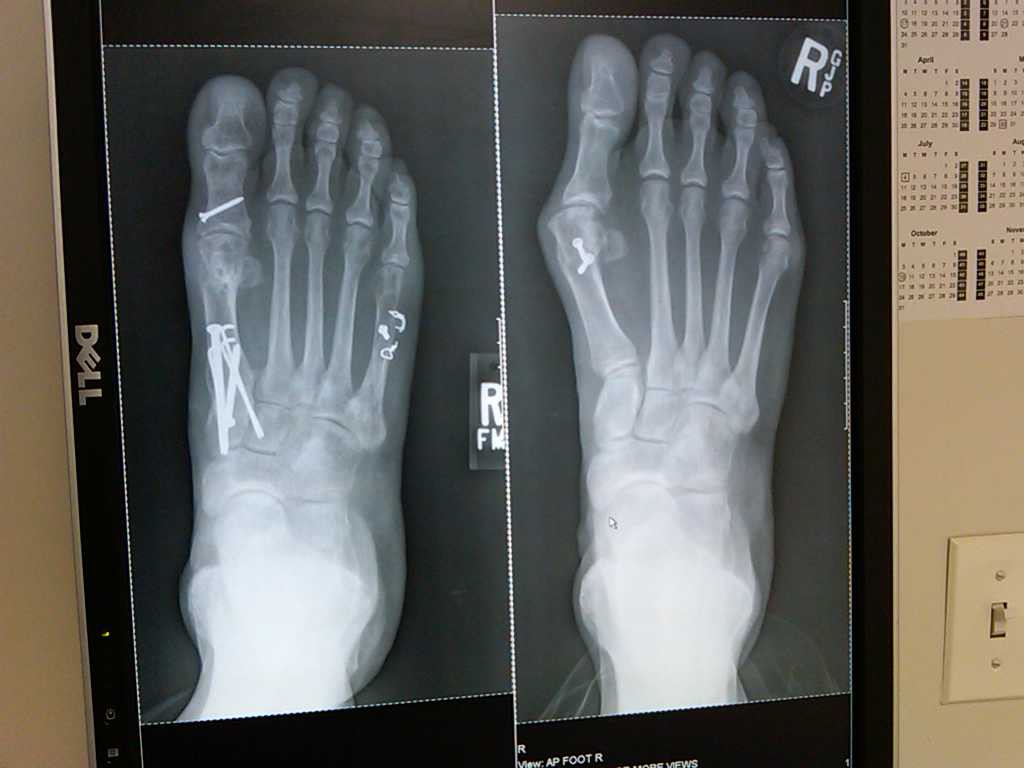

In October of 2014, I had surgery on the bunion on my left foot. Dr. Levine did an amazing job in the surgery and the recovery, while not exactly a walk in the park, was as easy as it could have been under the circumstances. A good friend had surgery on the same foot for the same thing at a different hospital and his foot still gives him pain today, over a year later. Eight weeks after surgery, my family and I vacationed in the Bahamas, and I was able to walk on the beach with my two boys. Fourteen months after surgery on Christmas Day of 2015, we climbed Machu Picchu together as a family!